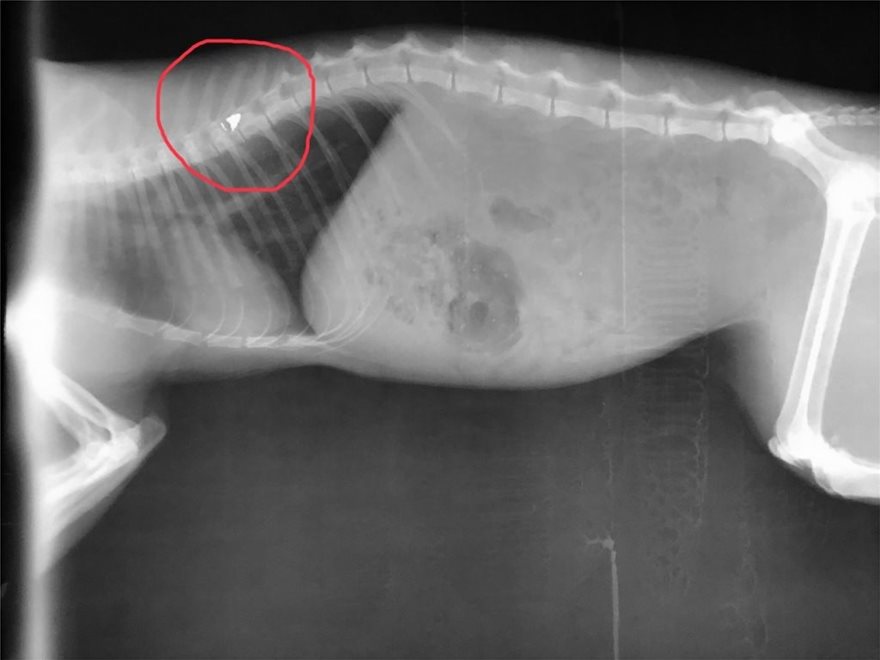

Μία γάτα στη Λαμία βρήκε τραγικό θάνατο, έπειτα από πυροβολισμό που δέχθηκε από διευθυντή λυκείου. Μετά τον πυροβολισμό, είχε προγραμματιστεί να πραγματοποιηθεί χειρουργείο για την αφαίρεση του βλήματος από αεροβόλο όπλο. Όμως, η γάτα, δεν κατάφερε να χειρουργηθεί. Αυτό, διότι άφησε νωρίτερα την τελευταία της πνοή.

Το άτυχο ζώο πυροβολήθηκε από τον δράστη με αεροβόλο όπλο την ώρα που ζευγάρωνε.